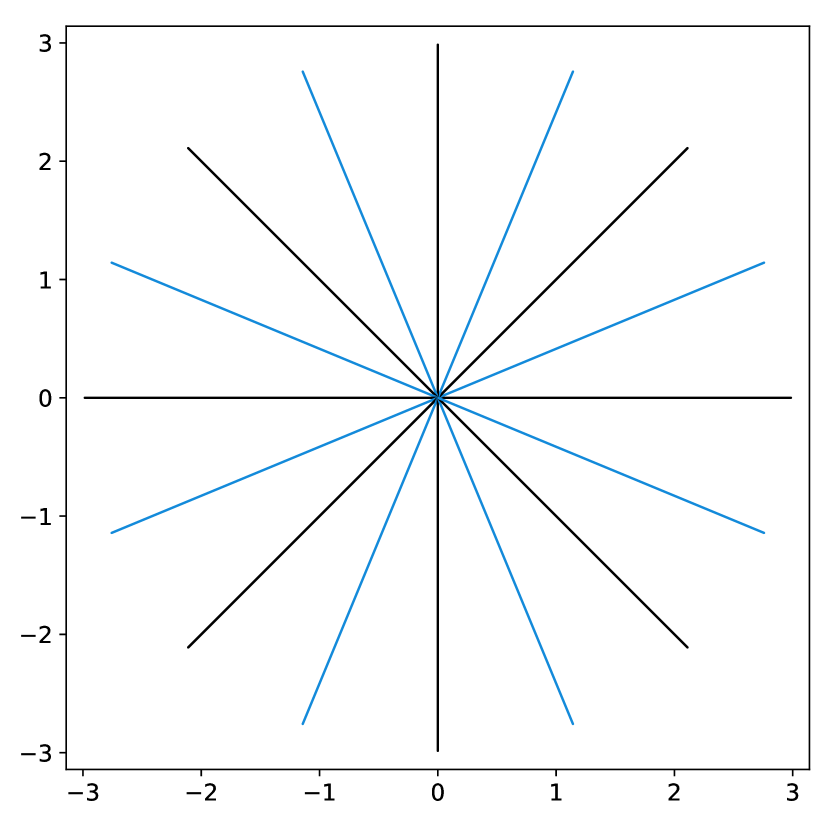

To illustrate this fact, we conducted a simple experiment in Fig. 1. Starting from two similar initial sampling trajectories, we let a multi-scale solver run for 14 epochs and 85 hours on the fastMRI knee database. We then evaluate the average reconstruction peak signal-to-noise ratio (PSNR) on the validation set. As can be seen, the final point configuration and the average performance varies by dB, which is significant. This suggests that the algorithm was trapped in a spurious local minimizer and illustrates the difficulty to globalize the convergence.

dB

dB